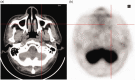

The relationship between antineutrophil cytoplasmic antibody (ANCA)-associated vasculitis (AAV) and lung cancer remains unclear. A 66-year-old man presented with pulmonary nodules. Histological examination of a specimen from computed tomography-guided percutaneous transthoracic biopsy revealed adenocarcinoma. The patient was treated using cryoablation and systemic chemotherapy. Sixteen months later, the patient presented with fever, nasal inflammation, recurrent lung lesions, elevated serum creatinine levels, and high levels of ANCA. Histological examination of a specimen from ultrasound-guided percutaneous renal biopsy revealed pauci-immune necrotizing crescentic glomerulonephritis. The patient responded to treatment, but granulomatosis with polyangiitis recurred and he later died. This case highlights the possibility of sequential AAV with lung cancer. Although this is relatively rare, further research is needed to better understand the association or pathophysiological link between lung cancer and AAV.